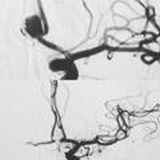

mosesmoscow@yandex.ru Эндоваскулярный нейрохирург, к.м.н. Аронов Моисей Саломонович Воспитанник школы НИИ им. Н. Н. Бурденко, руководитель отделения РХМДЛ в ФМБЦ им. А.И. Бурназяна